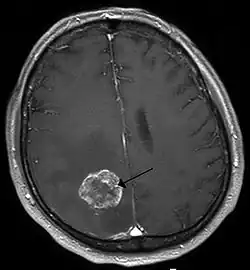

Nowotwory ośrodkowego układu nerwowego – grupa nowotworów rozwijających się w tkankach mózgowia i rdzenia kręgowego. Mogą to być nowotwory pierwotne i przerzutowe, nowotwory pierwotne dzielą się na łagodne i złośliwe. Inaczej niż w innych lokalizacjach, nowotwory łagodne ośrodkowego układu nerwowego również nierzadko wiążą się z poważnym rokowaniem, ponieważ mogą wywierać objawy uciskowe.